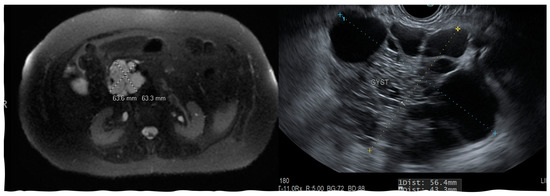

Figure 1.

Endoscopic ultrasound and CT scan images showing pancreatic pseudocyst near the uncinate process.